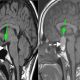

در صورت احتمال آسیب دیدن اعصاب در شکستگی یا تردید درباره علل درد، توصیه میشود بیمار MRI انجام دهد. اسکن MRI آزمایشی نسبتاً جدید است که از اشعه استفاده نمیکند. اسکن MRI با استفاده از امواج رادیویی و مغناطیسی تصاویری کامپیوتری ایجاد میکند. MRI قادر است از میان لایههای مختلف ستون فقرات عبور کند و هرگونه ناهنجاری در بافتهای نرم، مانند اعصاب و رباطها، را نشان دهد.